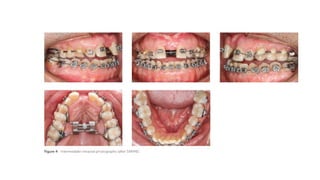

Pretreatment records

(age, 17 years 11 months).

(A) Facial photographs.

(B) Intraoral photographs.

Pretreatment records (age, 17 years 11 months).